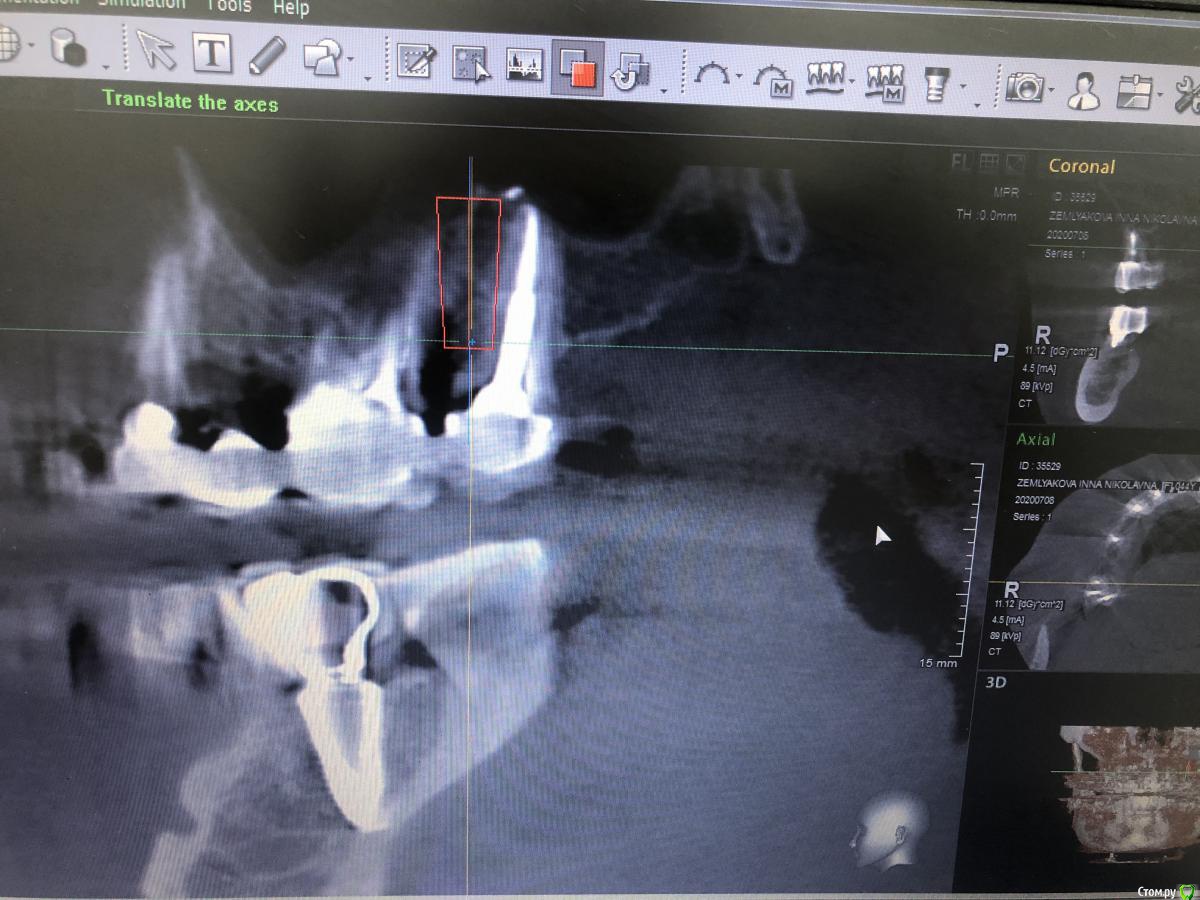

Nazim_NV86 Опубликовано 4 июля, 2020 Поделиться Опубликовано 4 июля, 2020 (изменено) Как расположить такой винт, чтобы не соприкасался с имплантом? Таблетку под углом к импоанту?1.Типа того2.У вас ФИО пациента видно. Желательно обрезать, то что выкладываете в сеть.3.Скачайте с оф сайта планмеки нормальную бесплатную версию. Там уже 6-я версия с мая этого года. И главное что ваш нарисованный план будет сохраняться. Изменено 4 июля, 2020 пользователем Nazim_NV86 2 Ссылка на комментарий

Александр07 Опубликовано 14 августа, 2020 Автор Поделиться Опубликовано 14 августа, 2020 Коллеги планируется имплантация на вч-удаление 2.4,2.6, 2.7 под ? ( ферула нет после снятие мк, можно попробовать удлинить но ортопед не особо настроен ) , здесь сложность в том что пац не может ходить без зубов, чтобы окружающие не знали об этом, Первый вариант это удаление 2.4-2.6 и капа , второй вариант это убрать 2.4,26.2,7 и импл с нагрузкой 2.4,2.5, 2.7 Вот срезы, скажите что думаете , насколько вероятно нагрузить и стоит ли, в обл 2.5 по хорошему откр с лифт, можно попробовать закрытый, 2.7 придётся смещать к перегородке межзубной Ссылка на комментарий